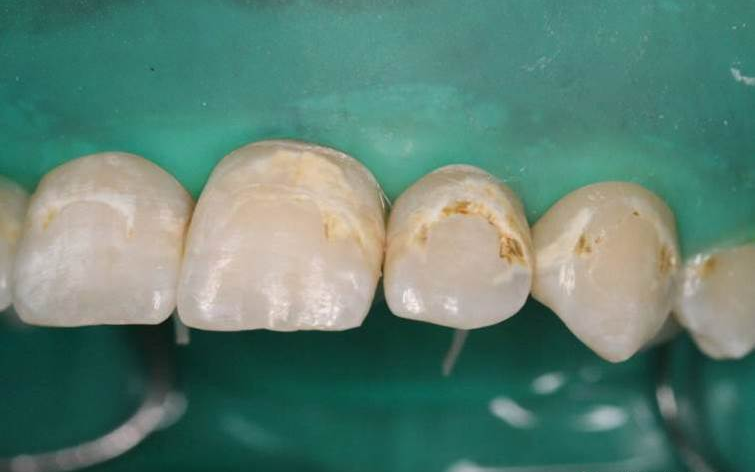

2、牙面清洁后,橡皮障隔湿

3、治疗部位涂布15%盐酸凝胶,酸蚀2分钟。2分钟后去除酸蚀剂,冲洗、干燥